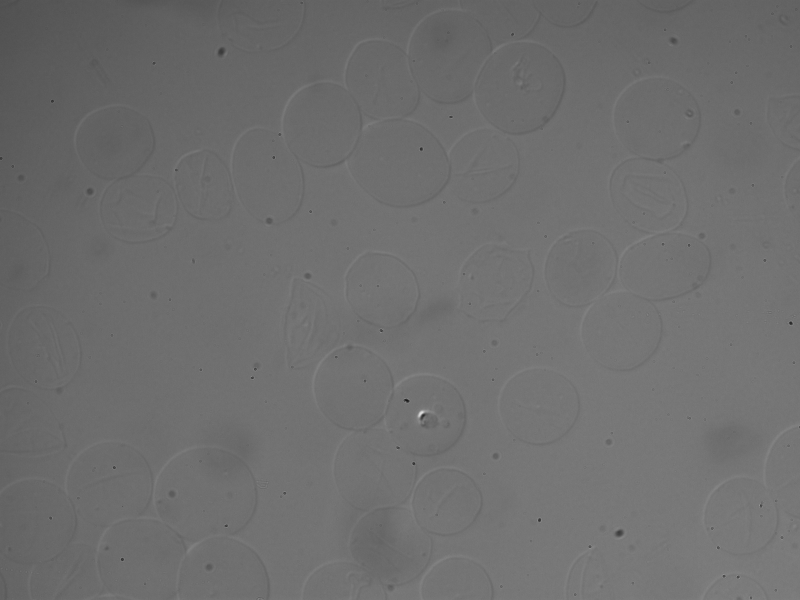

我依靠边缘检测(相对于颜色检测)从血细胞中提取特征。原始图像如下: